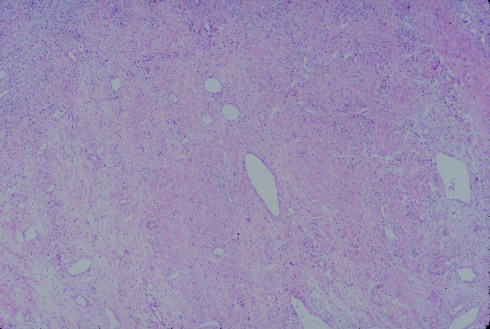

There are very few anatomical studies of the human gravid cervix. I think that more attention to the cervix at the time of gravid hysterectomy might yield some insight into cervical pathology, particularly the role of inflammation and changes in structure (Fig 1-3).

Fig 1: This is a low magnification of a gravid cervix with some myometrial cells to the right, then a denser fibrous area in the middle, and finally an area with loose stroma and many inflammatory cells. (H&E, 4x)